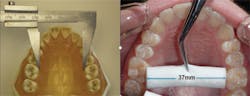

Orthodontist James McNamara, DDS, has provided the transverse measurement, which is the shortest distance between teeth Nos. 3 and 14 at the gumline. A healthy, uncrowded width falls in the range of 35 mm to 39 mm.4 Lesser measurements will result in crowding, the most common form of malocclusion. A quick way to gauge this would be to rest a cotton roll (37 mm) in between the maxillary first molars and evaluate the fit (figure 2).

Figure 2: Measuring the transverse measurement. Photo courtesy of Dr. Ben Miraglia.